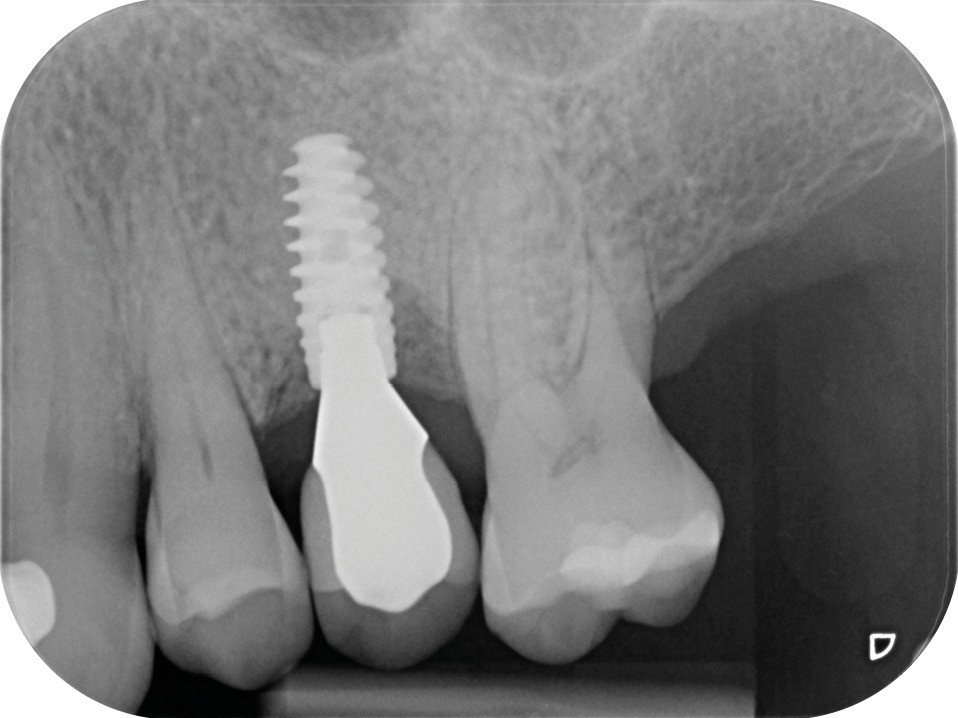

L’implant

- Posé en 2019 par son dentiste

- Couronne d’usage transvissée

- Péri-implantite diagnostiquée en 2020